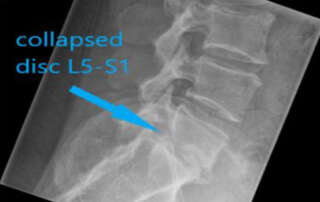

A parasitic fibroid and adhesions due to abdominal hernia surgery with mesh and tacker